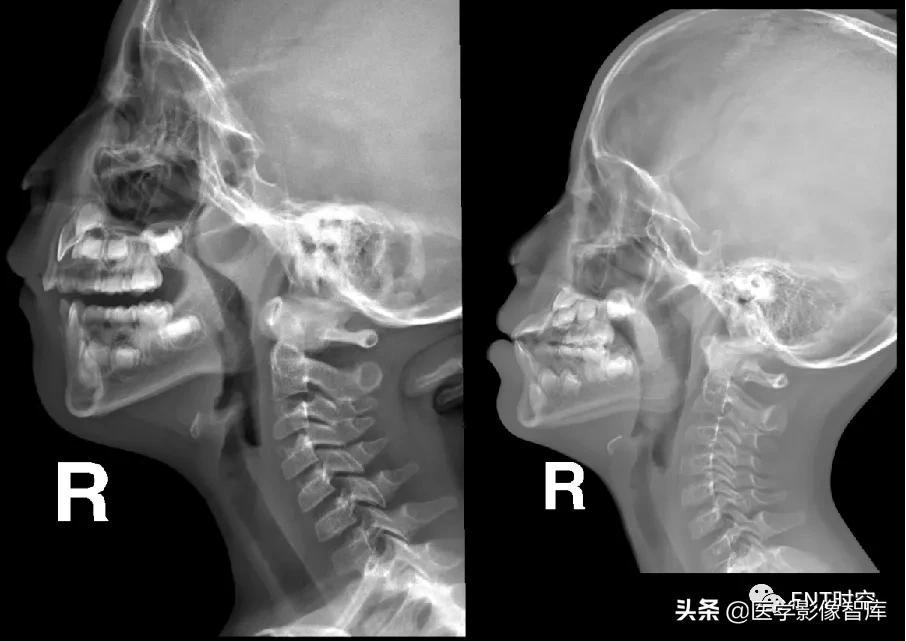

三、 鼻咽部侧位摄片优势:

1、能够很好的显示鼻咽腔宽窄情况

2、通过测量

腺样体(Adenoid,A)厚度

鼻咽腔(Nasopharyngeal,N)宽度

后气道间隙(Pharyngeal Airway Space ,PAS)

3、用腺样体-鼻咽腔比率A/N值及PAS宽度评估腺样体大小与鼻咽腔阻塞情况,为临床诊断和治疗腺样体肥大提供可靠的依据。

鼻咽侧位片的测量方法(一)

鼻咽侧位片的测量方法(二)

鼻咽后气道宽度(PAS)

软腭表面与腺样体表面最凸点之间有效气道宽度

作为PAS宽度 (图中a’),是鼻咽最小气道宽度

PAS宽度参考值:

- >10mm 属正常范围

- 6~10mm 腺样体生理性或中度肥大

- ≤5mm 腺样体重度肥大

- PAS≤3mm 患儿多有张口呼吸

- 有文献报道认为当A/N值≥0.71,PAS≤3mm可作为手术指征。